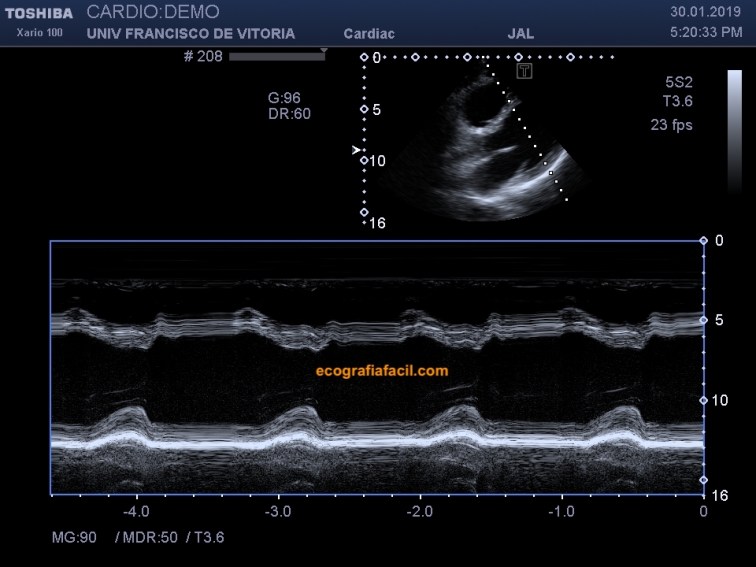

Además de la evaluación en 2D, es común obtener una imagen en modo M que pase por el borde libre de los velos de la válvula mitral y otra que pase por el centro del ventrículo izquierdo, como podéis ver en las figuras 7 y 8. Más adelante os explicaremos qué mediciones se pueden realizar en estos planos.

In addition to the 2D evaluation, it is common to obtain an M-mode image through of the mitral valve veils end -veils and another that passes through the middle of the left ventricle, as you can see in figures 7 and 8. More further on we will explain what measurements can be made in these plans.

Fig 8.